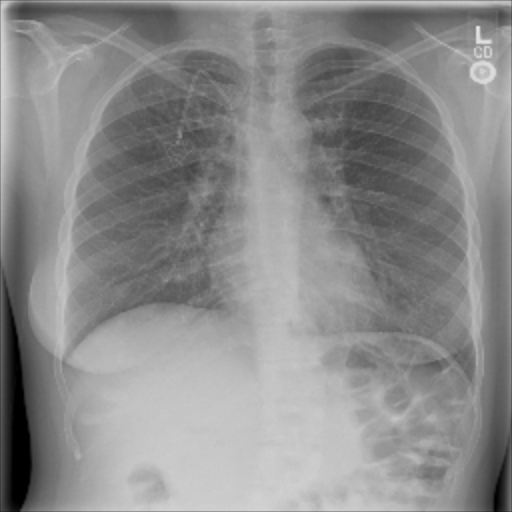

The data used in the following experiments consists of DICOM X-ray images, obtained from the University of Washington Medical Center and affiliated institutions, centered in Seattle by scanning radiology reports from the last three years. Inclusion criteria were: (i) Digital Radiography (DR) images, (ii) Chest radiographs, (iii) Posterior-anterior or anterior-posterior view position, (iv) Adult patients. Any personal health information was removed. Image-level labels were derived from natural-language processing based analysis of the reports. Cases were partially reviewed by a radiologist to confirm appropriate finding in the report’s impression section and this represented a critical finding. The resulting dataset contained 1003 images: 437 with pneumothorax, 566 with a different or no abnormality detected. We generated pixel-level annotations of the pneumothorax region for 305 of the positive cases. For training and evaluation, we divided the dataset into five cross-validation splits of similar size, such that images of the same patient resided in the same split.